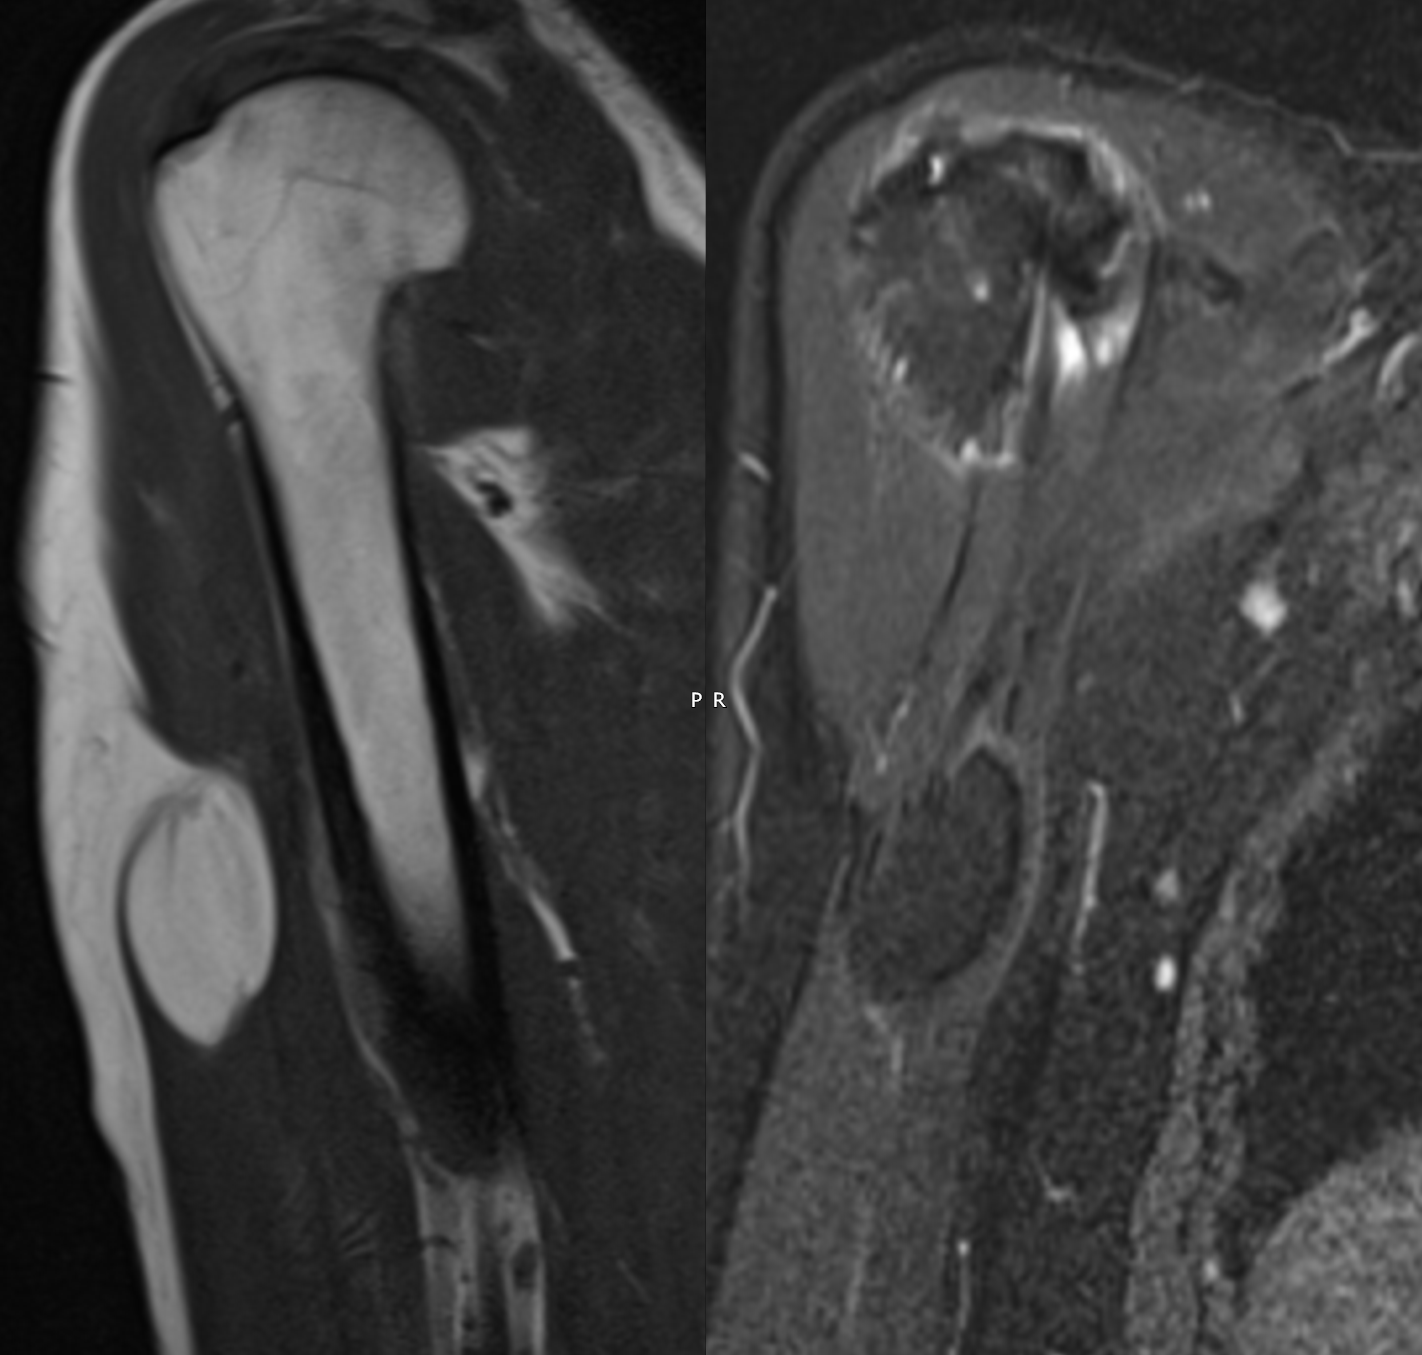

Intrabicipital lipoma Szerző: admin | aug 30, 2015 | Lump and bump, MSK, Muscular, SOL | Nincsenek hozzászólások T1w Sag & T1 FS Cor T1w Axi & T1w FS Axi & USS Sag The soft tissue mass anteriorly in the right upperarm is an approximately 4 cm intramuscular simple lipoma in biceps muscle. No features of sarcomatous change.